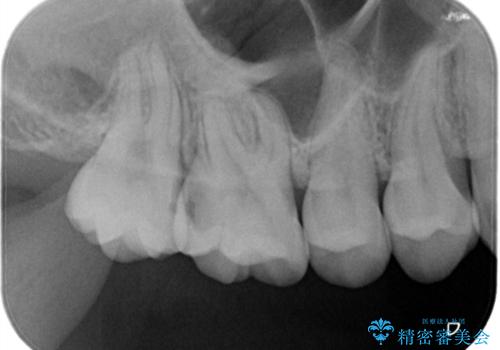

他院で入れたインレーの下にむし歯、ゴールドインレーで修復

- 定期検診にて他院で入れたインレーの下にむし歯を認め治療を行なっております。

拡大視野下で虫歯を除去し、ゴールドインレーにて修復治療を行なっております。